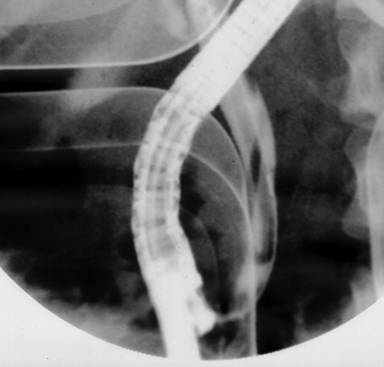

A 33-year-old healthy woman was born and lives in Bangkok which is the largest urban area of Thailand. She works as a secretary of a private company. She loves eating fresh vegetables. She had the history of intermittent epigastric pain for two months and presented with severe abdominal pain radiating to her back with nausea and vomiting for one day. Physical examination revealed febrile (37.5°C), no jaundice, marked tenderness at epigastrium and decreased bowel sound. Laboratory testing results showed leukocytosis of 11.7 x103/µL (reference range: 4.0-11.0 x103/µL) with 72% granulocytes (reference range: 40-74%) and 3% eosinophil (reference range: 0-7%), AST 105 U/L (reference range: 0-40 U/L), ALT 157 U/L (reference range: 0-40 U/L), alkaline phosphatase 229 U/L (reference range: 32-92 U/L), total bilirubin 1.4 mg/dL (reference range: 0.3-1.2 mg/dL), direct bilirubin 1.0 mg/dL (reference range: 0-0.5 mg/dL) and serum amylase 2,036 U/L (reference range: 0-220 U/L). Stool testing for parasites and ova were negative for three days. Abdominal computed tomography (CT scan) showed dilated common bile duct (0.8 cm in diameter) without filling defects and no gallstone. No evidence of acute pancreatitis was found from this study. She was initially diagnosed with acute mild gallstone pancreatitis with suspected retained common bile duct stone by over all clinical manifestations. Endoscopic retrograde cholangiography was performed and swollen ampulla with purulent bile were noted (Figure 1). Cholangiogram showed dilated common bile duct of 1.2 cm and there was a cylindrical filling defect about 6-7 cm in length inside the common bile duct (Figure 2). After endoscopic sphincterotomy, the parasite popped out and was extracted, using an extraction balloon catheter, then removed with a snare. The cholangiogram after removing this parasite showed markedly decreased in size of common bile duct without residual filling defect. The parasite in duodenum was shown in Figure 3. It was identified as a 22 cm long adult form of Ascaris lumbricoides (Figure 4).

Figure 1. Endoscopic retrograde cholangiopancreatography showing a cylindrical filling defect (arrows) on the dilated common bile duct. |